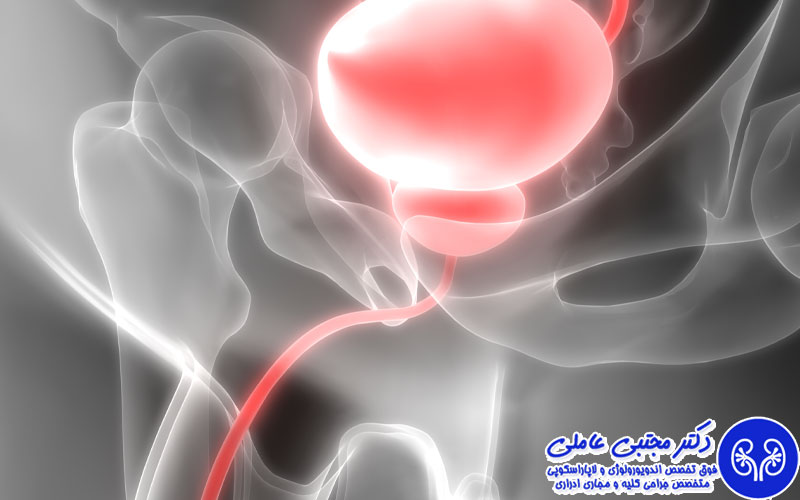

دیورتیکول مثانه عارضه ای است که در دیواره مثانه اتفاق می افتد. دیورتیکول شبیه به حباب یا کیسه ای به نظر می رسد که از دیواره داخلی مثانه بیرون زده است. دیورتیکول مثانه دو نوع کاذب و واقعی دارد. در دیورتیکول واقعی تمامی لایه های تشکیل دهنده دیواره مثانه در کنار هم باعث تشکیل حباب یا کیسه می شوند اما در دیورتیکول کاذب حباب ها تنها بر اثر غشای مخاطی بیرونی تشکیل می شوند.

- ریفلاکس ادرار به کلیه

- انسداد خروجی مثانه: بزرگی غده پروستات یا تنگ شدن مجرای ادراری باعث می شوند تا خروجی مثانه مسدود شود و به مرور زمان کیسه های دیورتیکول روی دیواره آن شکل بگیرند.